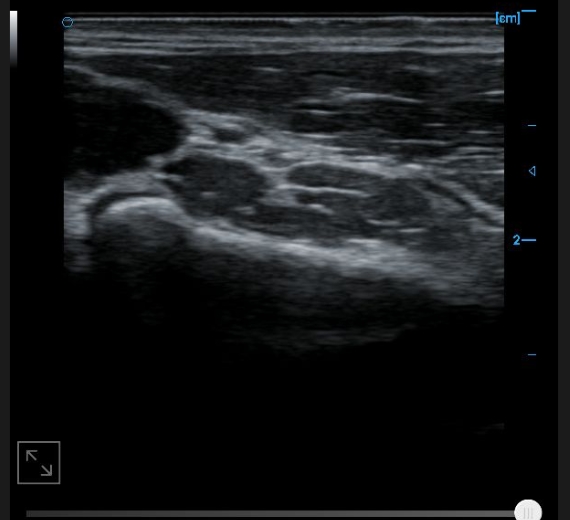

Internal testing supports images with B

External testing supports images with B

Posterior tibial tendon B image

Posterior calcaneal bursa B image

Image of anterior tibiofibular ligament B

Image of anterior talofibular ligament B